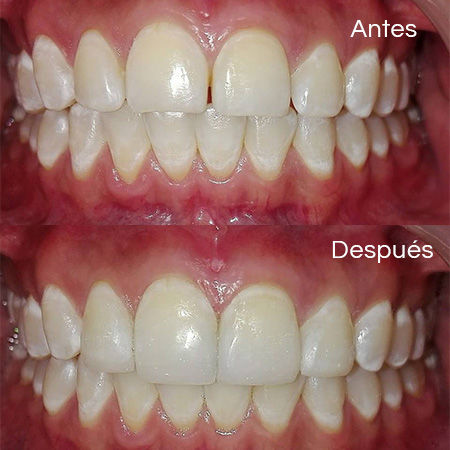

Before and After Gallery